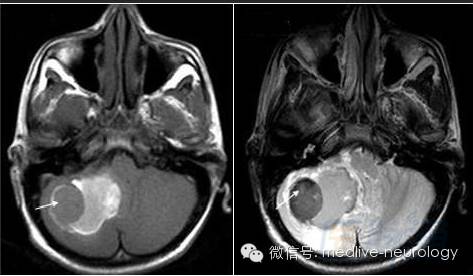

慢性期(>14d):箭头